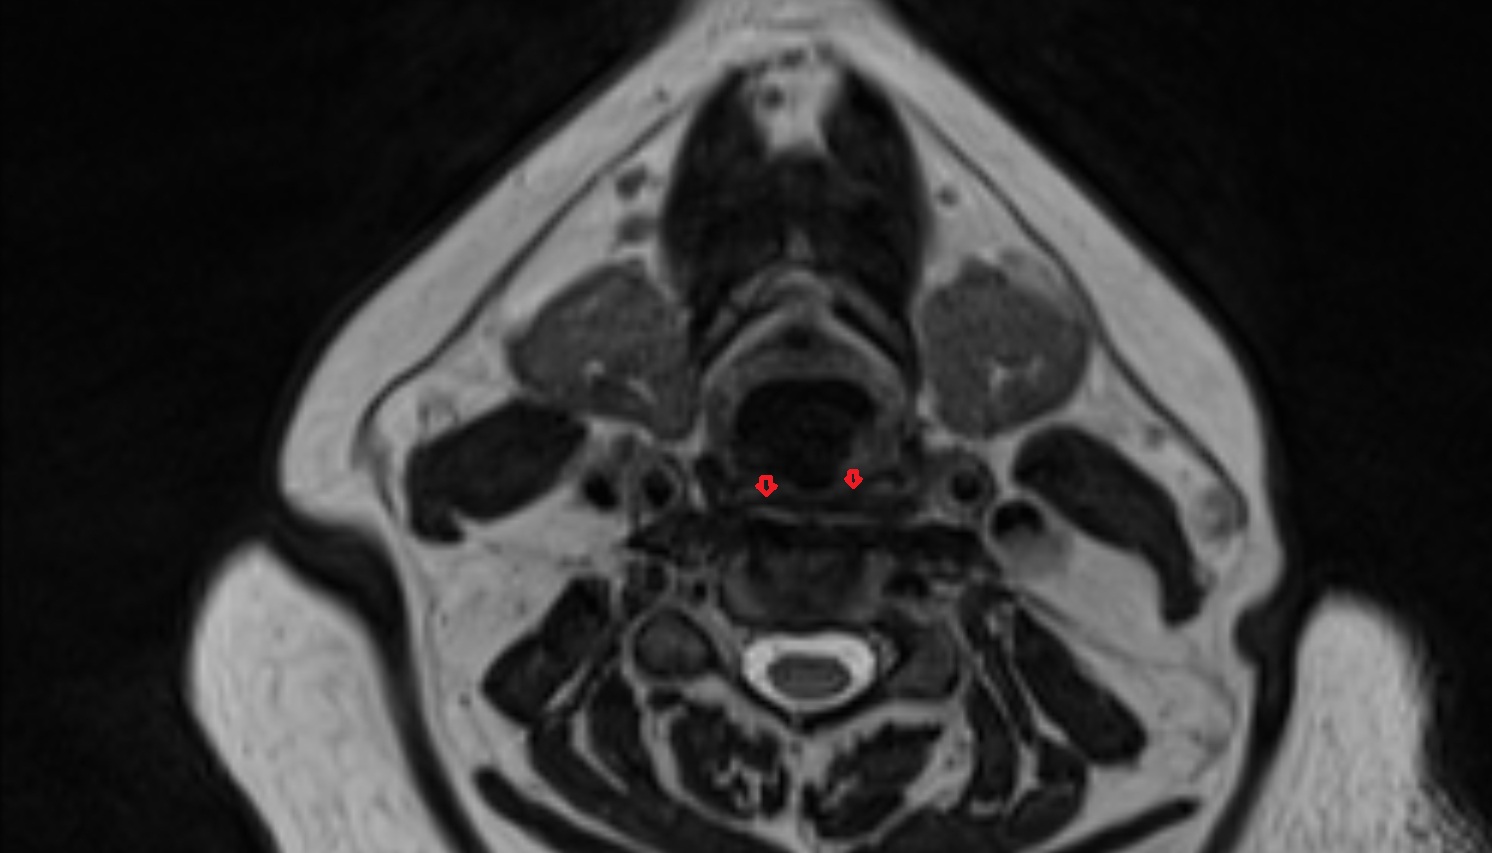

- Meckel’s cave (Trigeminal cave)